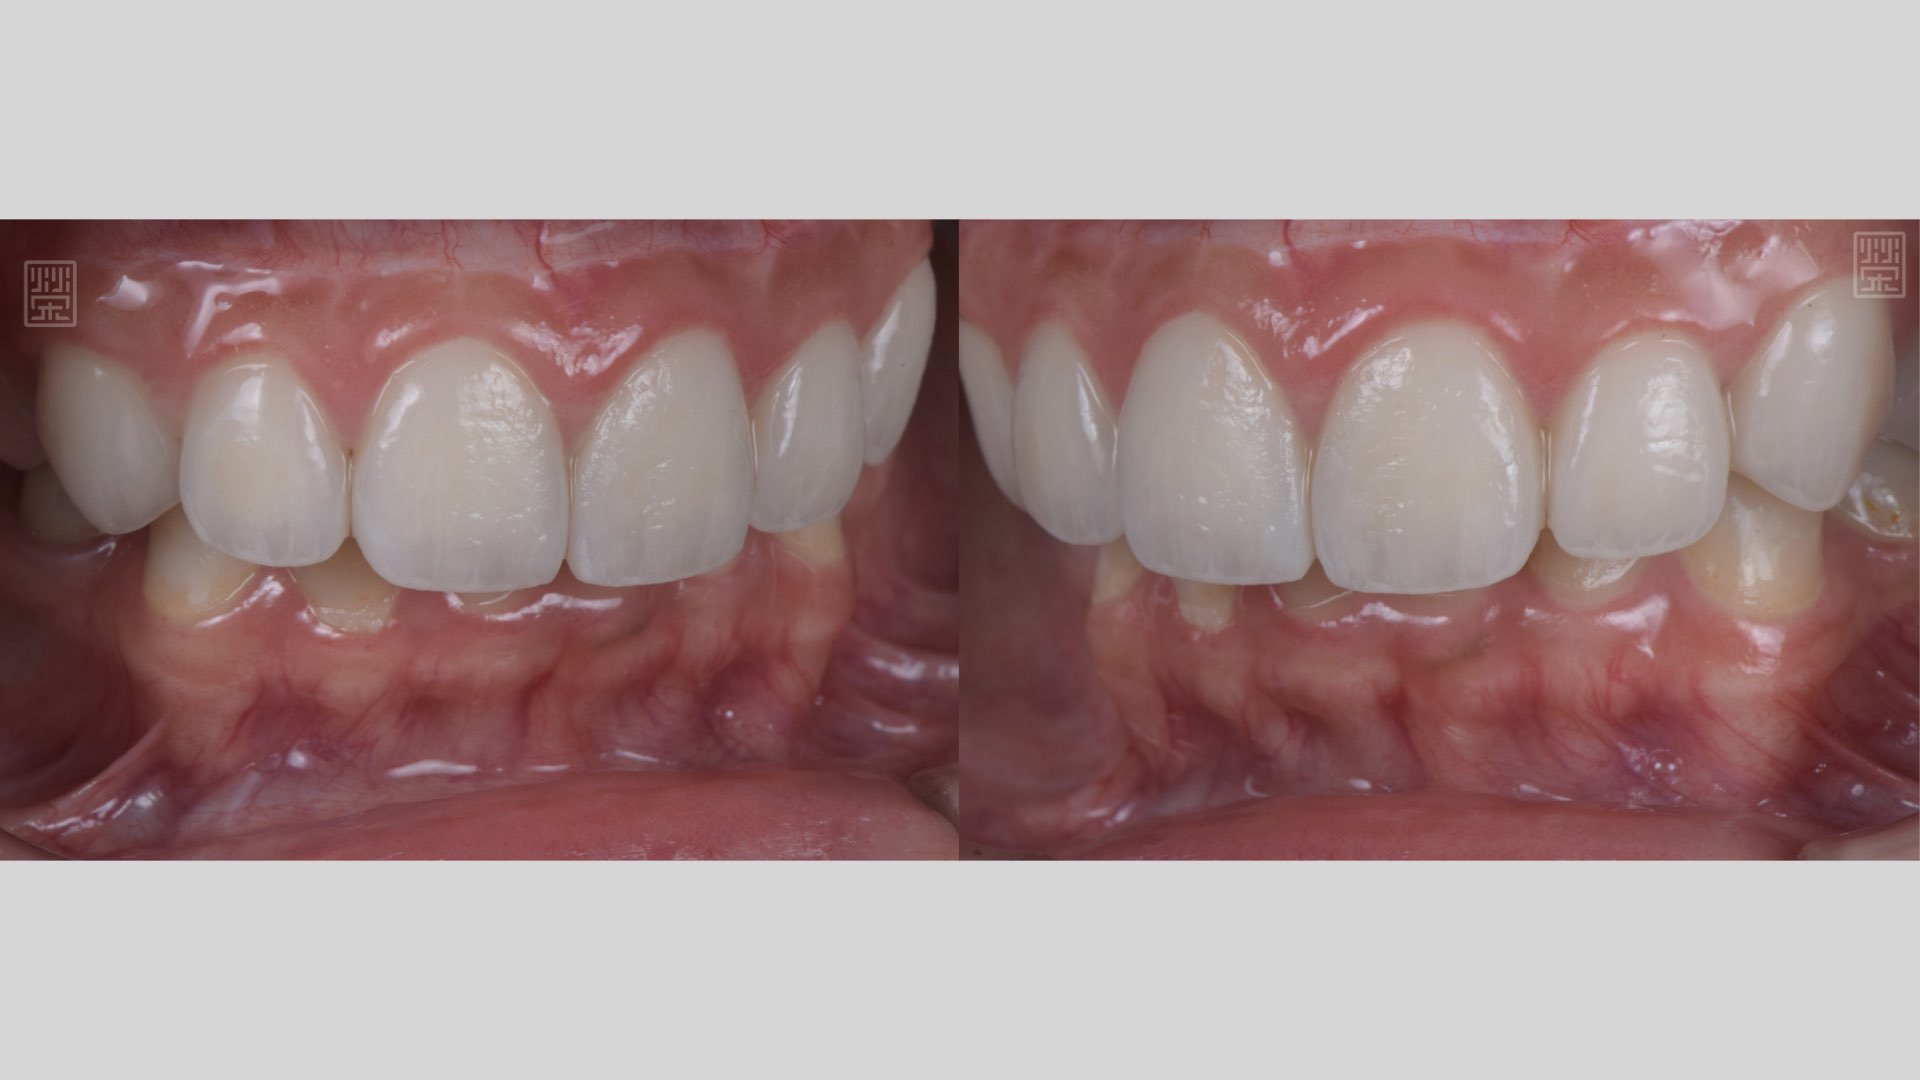

微笑曲線建立

全瓷貼片完成